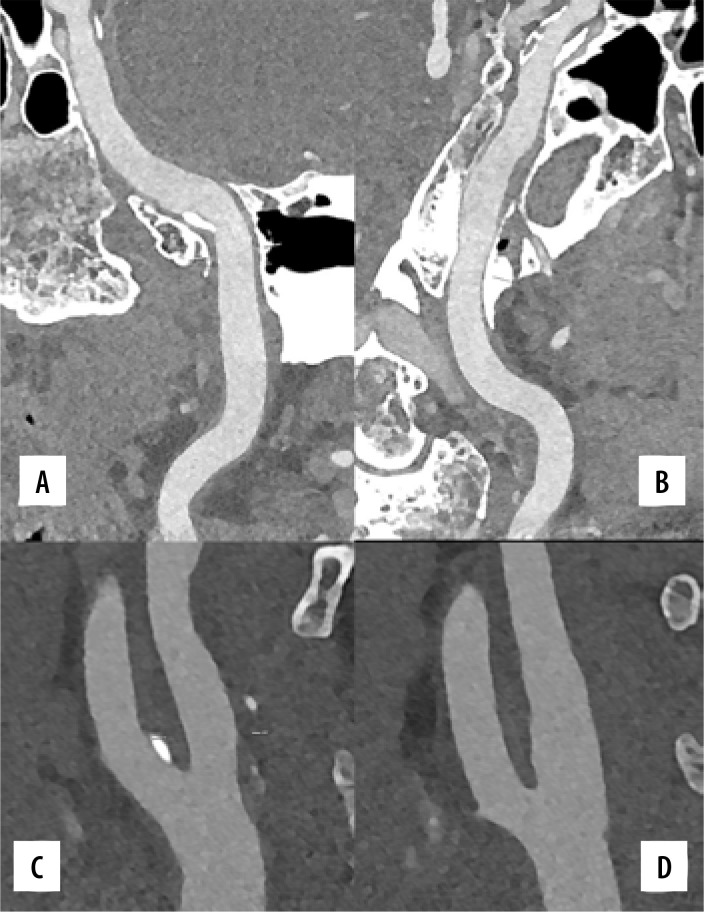

Photon-counting detector computed tomography (PCD-CT) devices have recently been introduced into practice, despite photon-counting detector technology having been studied for many years. PCD-CT devices are expected to provide advantages in dose reduction, tissue specificity, artifact-free imaging, and multi-contrast demonstration capacity. Noise reduction and increased spatial resolution are expected using PCD-CT, even under challenging scanning conditions. Some experimental or preliminary studies support this hypothesis. This pictorial review illustrates the features of PCD-CT systems, particularly in the interventional field. PCD-CT offers superior image quality and better lesion discrimination than conventional CT techniques for various conditions. PCD-CT shows significant improvements in many aspects of vascular imaging. It is still in its early stages, and several challenges have been identified. Also, PCD-CT devices have some important caveats. The average cost of these devices is 3 to 4 times higher than conventional CT units. This additional cost must be justified by improved clinical benefits or reduced clinical harms. Further investigations will be needed to resolve these issues.